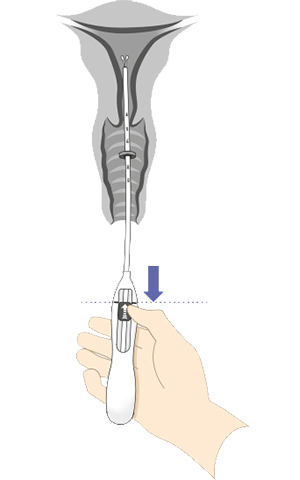

Énhånds innføring med Bayer-innføringssystem

Det integrerte innføringssystemet gjør det mulig for deg som lege, jordmor eller helsesykepleier å klargjøre innlegget med én hånd. Innføringshylsens diameter er 3,8 mm

8 trinn for riktig plassering av Kyleena